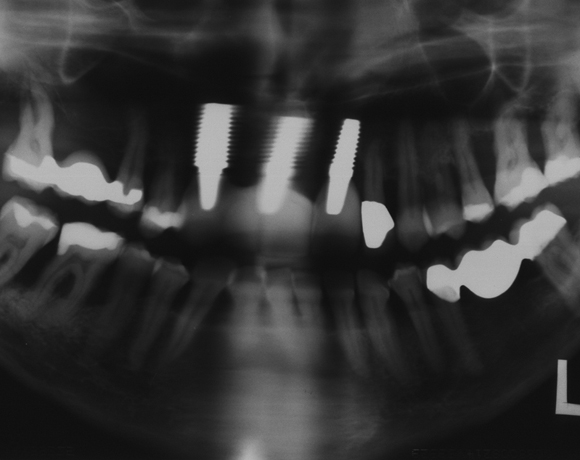

Als Ersatz wurden drei Implantate für die Zähne 13, 11, 21 gesetzt, die Lücke 15 – 17 mit einer

vollkeramischen Brücke versorgt. da die Patientin eine metallfreie Versorgung wünschte,

wurden Zeramex C Implantate gewählt, auch der Zahn 22 wurde mit einer vollkeramischen

Krone versorgt.